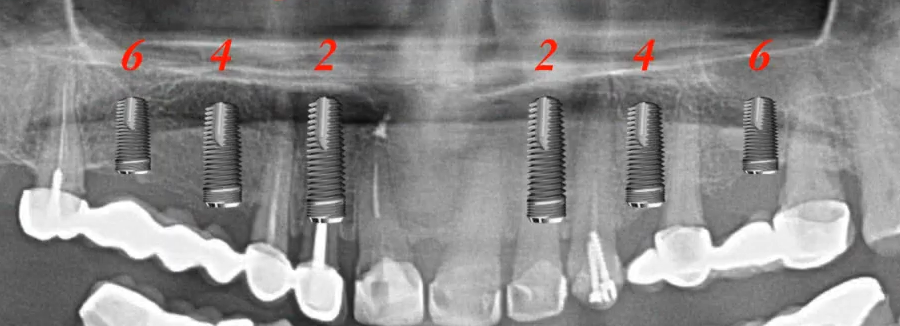

- Guidelines for implant positioning in the upper jaw. It’s best to place six implants in positions 2, 4, and 6.

An example of optimal implant positioning in the upper jaw. YouTube/Dr. Sergey Rozhnov /sergiodontolog

But if there is a deficiency of bone tissue in the distal sections, which is typical for the upper jaw, then displacement in the positions of teeth 1, 3, 5 is allowed.

If the patient is petite, four implants in positions 2 and 5 may be sufficient. In some cases, as with the lower jaw, a single implant can be placed centrally to provide five points of support. However, it should be noted that, unlike the lower jaw, the upper jaw has a Sutura intermaxillaris, which remains mobile throughout life in many patients. Therefore, placing the implant precisely in the center between the central incisors is not recommended. A formula of 1, 3, 5 in one quadrant and 3, 5 in the other can be used.

The 3.6 formula is rarely used for the upper jaw. The upper jaw is always wider, and the distance between implants would be too large.